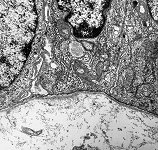

Miniaturbildübersicht Luftröhre (Trachea) Bronchien & Bronchiolen:

Bronchialepithel

(Ratte)

idem (Ratte)

hochauflösende Rekonstruktion einer Bronchialepithelzelle (Ratte) Detail unten  Detail Mitte 1 Detail Mitte 2 Detail oben

Die Luftröhre (Terminologia histologica: Trachea; englisch: trachea) leitet die Atemluft zur Lunge. Sie beginnt nach dem Ringknorpel des Kehlkopfes (Cartilago cricoidea) und endet an ihrer Verzweigung in die Hauptbronchien der rechten und der linken Lunge. Das Innere der Trachea wird von einer respiratorischen Schleimhaut (Terminologia histologica: Tunica mucosa respiratoria; englisch: respiratory mucosa) ausgekleidet. Nur im Bereich der Luftröhrengabelung am Abgang der Hauptbronchien findet sich normalerweise mehrschichtig unverhorntes Plattenepithel aufgrund der hier das Epithel stark beanspruchenden Luftwirbelbildung. Ansonsten zeigt die respiratorische Schleimhaut ein mehrreihiges Flimmerepithel, also mit Kinocilien versehene Epithelzellen, deren Kerne in mehreren Reihen angeordnet sind, wobei die hochprismatischen Zellen alle Kontakt zur darunterliegenden Basalmembran haben. Im Epithel der Trachea kommen auch Becherzellen (Terminologia histologica: Mucocyti, Exocrinocyti caliciformes; englisch: mucous cells, goblet cells) und vereinzelte neuroendokrine Zellen (Terminologia histologica: Neuroendocrinocyti respiratorii; englisch: respiratory neuro-endocrine cells) vor, die in ihren basalen ZytoplasmaSekretvesikel mit Serotonin und verschiedenen Neuropeptiden speichern und nach basal ins Bindegewebe und damit letztlich auch Blut abgeben. Diese Zellen gehören zum diffusen neuroendokrinen System und können sich zu größeren Gruppen zusammenschließen, die dann als neuroepitheliale Körperchen (Terminologia histologica: Corpora neuroepithelialia; englisch: neuroepithelial bodies) bezeichnet werden. Hier aber auch in der gesamten Lamina propria finden sich viele afferente Fasern des Nervus vagus, was für die Auslösung des Hustenreflexes wichtig ist. An einigen Stellen sind im Epithel die Mündungen der Ausführungsgänge von kleinen seromukösenTrachealdrüsen (Terminologia histologica: Glandulae tracheales; englisch: tracheal glands) zu erkennen, deren Endstücke sowohl muköse Zellen (Terminologia histologica: Mucocyti; englisch: mucous cells) als auch seromuköse Zellen (Terminologia histologica: Seromucocyti; englisch: seromucous cells) und Myoepithelzellen (Terminologia histologica: Myoepitheliocyti; englisch: myoepithelial cells) zeigen. Die Drüsen kommen vor allem im Bereich des Paries membranaceus oder der die einzelnen Knorpelspangen verbindenden Bänder (Terminologia histologica: Ligamenta anularia; englisch: anular ligaments) vor und liegen zumeist in der unter dem Epithel gelegenen Schicht aus lockerem Bindegewebe (Terminologia histologica: Lamina propria; englisch: lamina propria). Hier finden sich neben einigen Fibrozyten auch ein paar mobile Bindegewebszellen, deren Zahl bei Atemwegsinfekten drastisch ansteigt. Außerdem kommen hier neben kollagenen auch viele meist längs orientierte elastische Fasern vor.